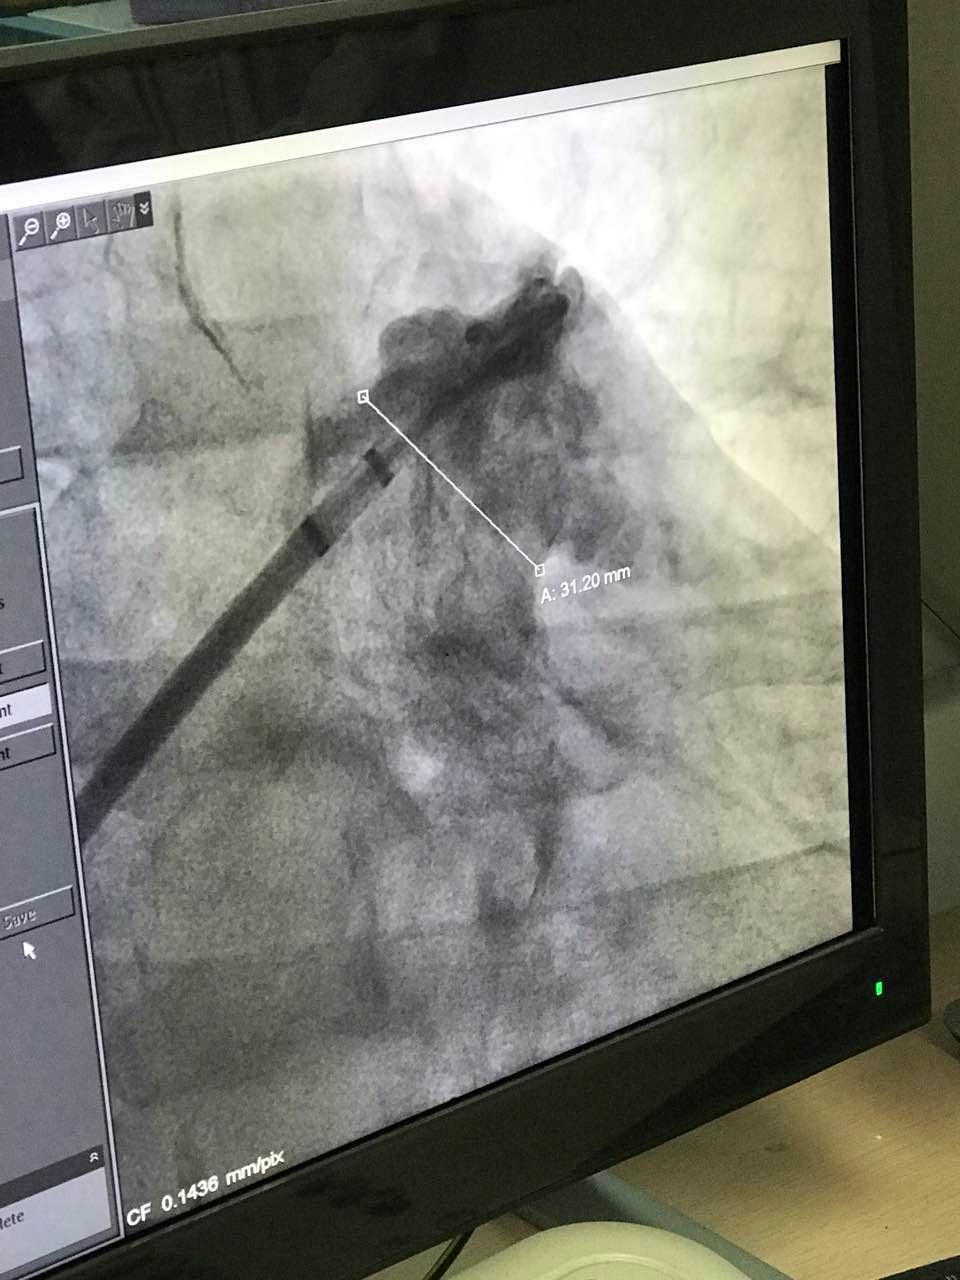

接受手术的患者为一名63岁男性,被诊断为心律失常,其心房纤颤伴有快速心室率,心功能为2级。经食道超声测量患者左心耳开口直径为31.2mm,左心耳深度约为10mm,为鸡翅型心耳结构。因患者左心耳开口大,深度浅,具有丰富临床经验的武汉大学人民医院心血管内科黄鹤主任和来自香港的林逸贤医生选用型号为3640的LAmbre™左心耳封堵器对患者实施封堵,用时不到40分钟便顺利完成整个手术。LAmbre™型号为3640的左心耳封堵器为目前已上市的尺寸最大的左心耳封堵器,为大心耳的患者提供了安全有效的手术解决方案。

图:术中造影